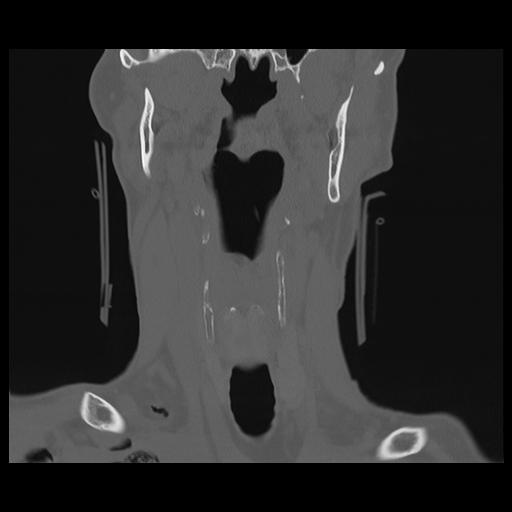

16 HUESO,,Coronal,2.000,HUESO,Coronal,